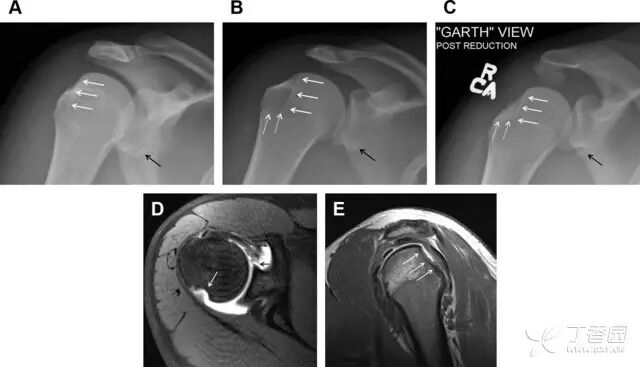

肩关节是最容易脱位的关节之一,肩关节脱位常伴随其它结构的损伤,如血管神经损伤、肩袖损伤、盂唇损伤、Bankart 损伤等。脱位本身诊断往往是明确的,容易被忽略的是其继发的伴随损伤。

需要仔细评估肱骨头、大结节、关节盂边缘、肩峰、喙突等结构。典型的 X 线投射角度包括:内旋位前后位片、外旋位前后位片(Grashey 位)、侧位(肩胛骨 Y 位)、腋位片以及改良腋位片。

图 6 肩关节前脱位伴有 Hill–Sachs 和 Bankart 损伤:(A~C)肱骨头后外侧撞击骨折,白色箭头所示为骨折的内侧边界;(A)内旋位前后位片,(B)「V」形压缩骨折的下边界(虚线短箭头),(C)Garth 位(轴向投影)示 Hill–Sachs 损伤(虚线和实线折箭头),特别是对骨性 Bankart 损伤的诊断有帮助。(D、E)MRI 进一步证实了损伤

图 7 肩关节后脱位伴有反 Hill–Sachs 损伤。(A)外旋位前后位片可见一硬化带(黑箭头),此「凹槽征」与肱骨头关节面平行;(B)腋位片进一步证实了骨折的存在